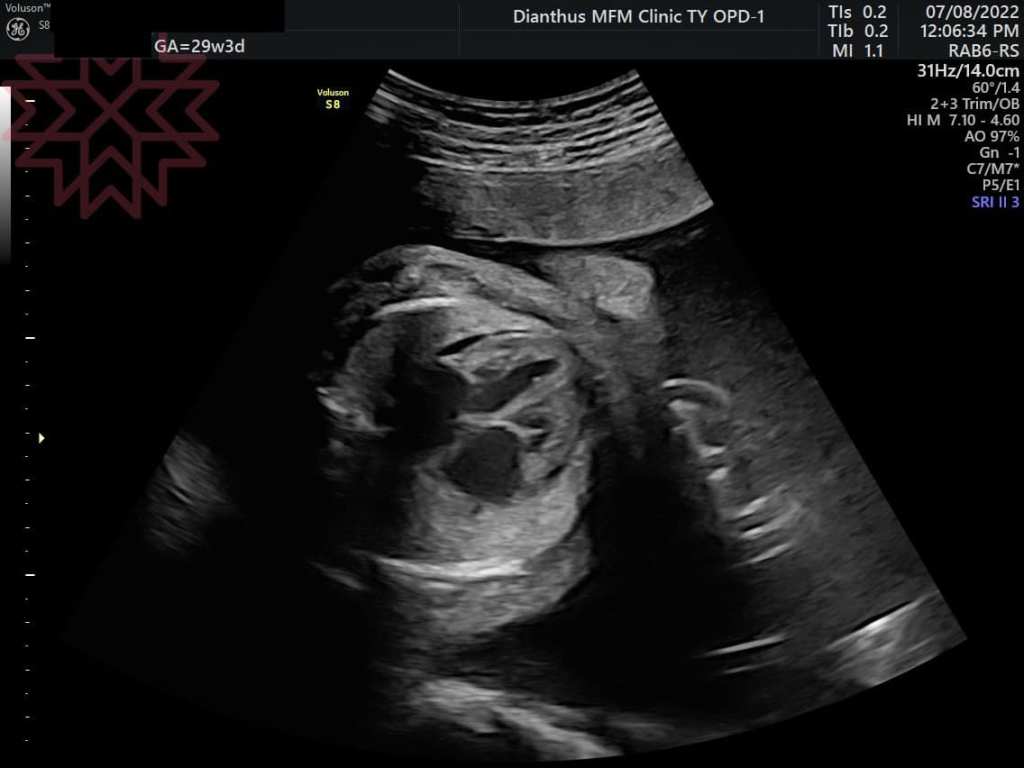

甚至到29週的時候

寶寶的心臟不堪負荷產生心臟衰竭

開始有腹水及胎兒水腫的狀態(如圖)(細節就不說了)